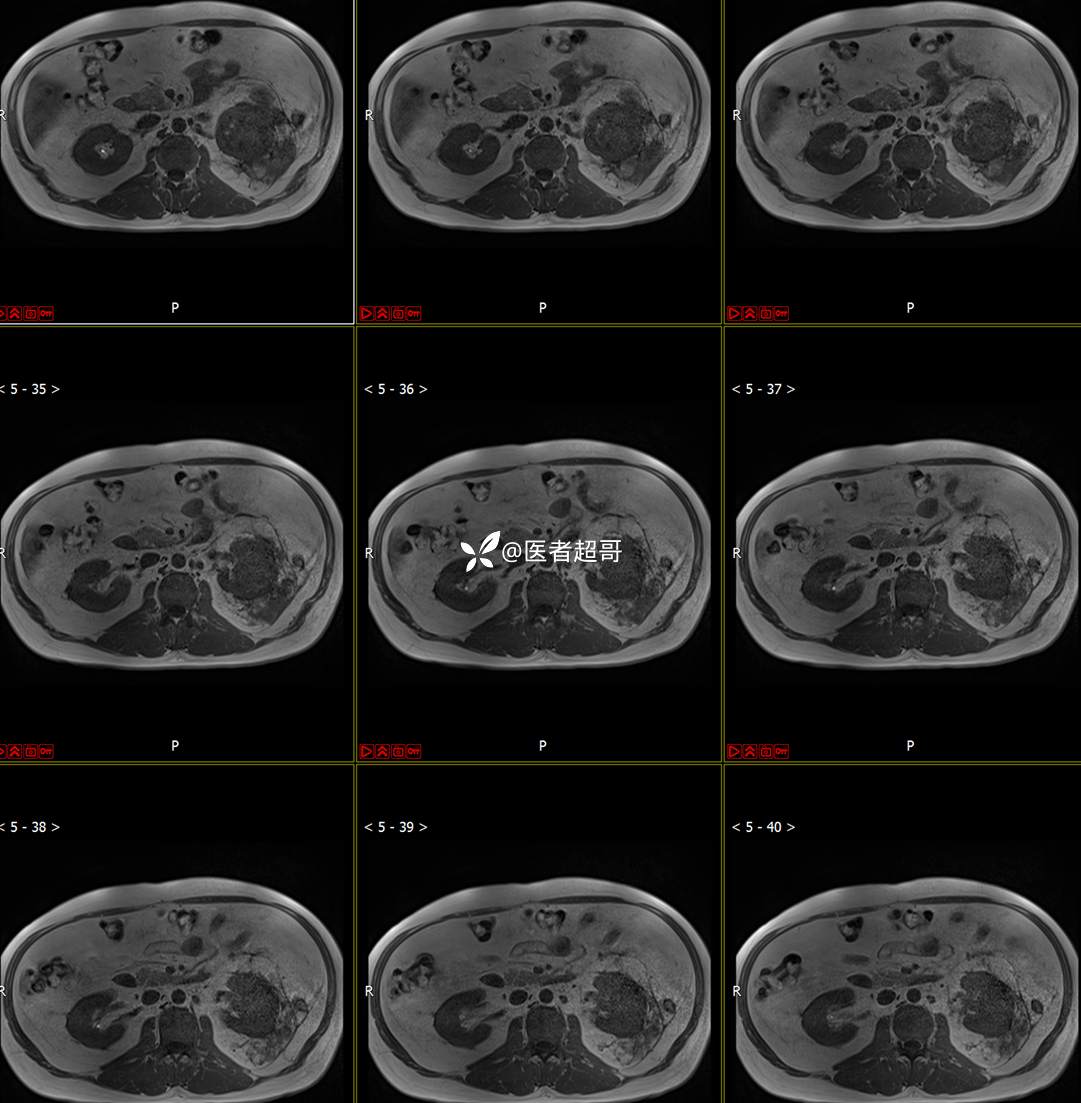

主 诉:查体发现左肾肿物9天。

现病史:患者9天前于附属医院行常规腹部CT检查时,发现左肾占位性病变并肾周脂间隙软组织增多,自述无明显腰腹部不适,无尿频、尿急、尿痛及肉眼血尿,未予特殊治疗,患者近期无头晕头迷,胸闷气急,腹胀腹泻及其他部位明显不适,遂至我院就诊,门诊以“肾肿物”收入院,患者自发病以来,精神可,睡眠饮食可,大便正常,体重无明显减轻。